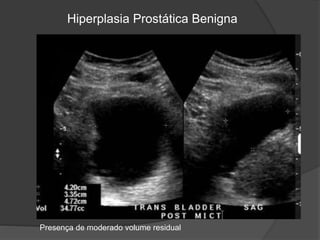

Hiperplasia Prostática Benigna

Presença de moderado volume residual